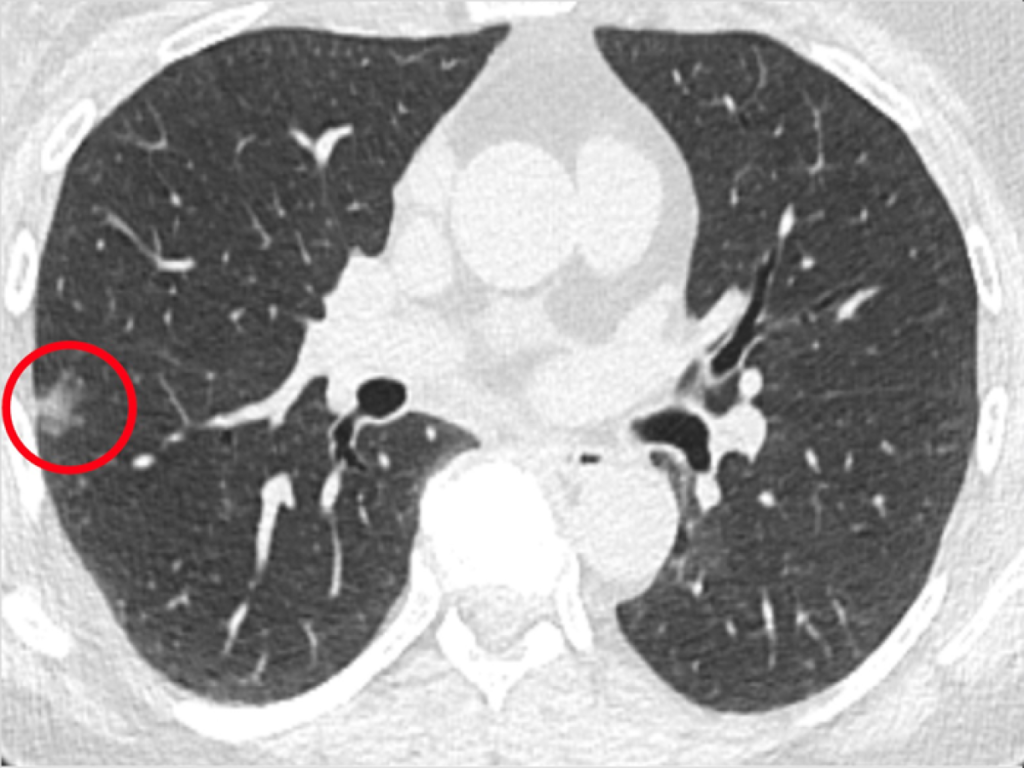

Cientistas descobrem forma de identificar câncer de pulmão mais cedo

O diagnóstico do câncer de pulmão acaba de ganhar uma facilidade que pode salvar a vida de muitas pessoas. Pesquisadores do Abramson Cancer Center, da Universidade da Pensilvânia, nos Estados Unidos, descobriram uma maneira de identificar o câncer de pulmão mais cedo, ainda no nível celular, em tempo real durante uma biópsia. Isso significa que […]